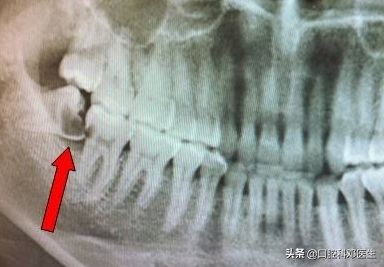

智齿是人类正常的牙齿,随着人类的进化,人从爬行到站立,从生食到熟食,从粗粮到细粮,其中骨头、牙齿、肌肉的进化不完全同步,脸蛋越来越小,导致骨量与牙量不协调,骨头内不能容纳更多的牙齿,特别是最后萌出的智齿。

智齿没有足够的空间萌出,只能部分萌出,或者完全埋伏在骨头内,这就为智齿发炎留下了病根,只要抵抗力下降,就会引起细菌大量繁殖,引起智齿区域的疼痛。

很多人认为智齿是好好的牙齿,为什么要拔掉呢?或者是担心拔牙痛,一直下不了决心,导致越拖越厉害,引起了很多本不该出现的问题,比如留着智齿引起旁边牙齿的蛀牙、疼痛;留着智齿引起的囊肿、肿瘤;留着智齿引起的牙齿拥挤;留着智齿等到怀孕发炎时的痛不欲生;留着智齿引起的骨髓炎、面部瘘管等;